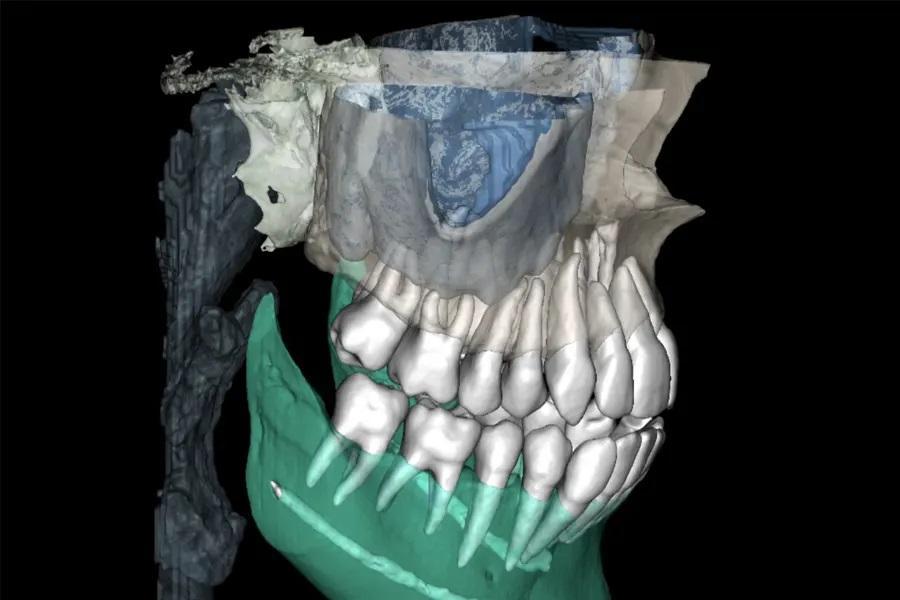

Фото 4. Скрининг дыхательных путей по КЛКТ (иллюстративные срезы), демонстрирующий высокое небо, узкую зубную дугу и V-образную форму. У пациентки отмечались переднее положение языка при глотании и ограничение его подвижности в средней трети. Было начато миофункциональное лечение.